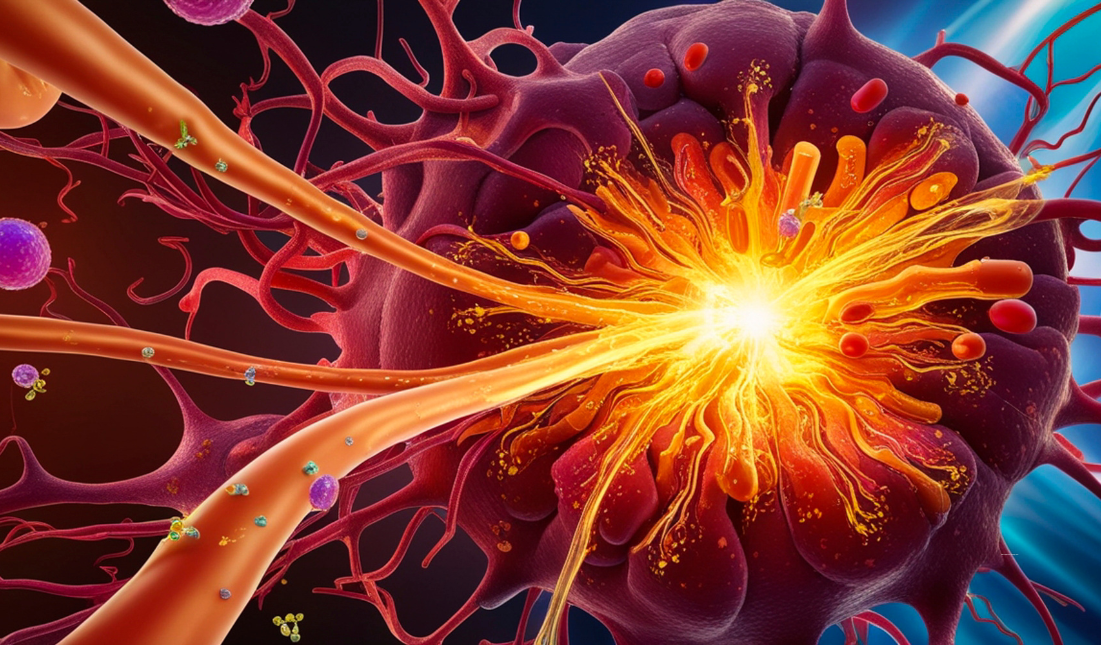

Read MoreBreaking New Ground

Home Head and neck cancers affect thousands of individuals globally, but thanks...